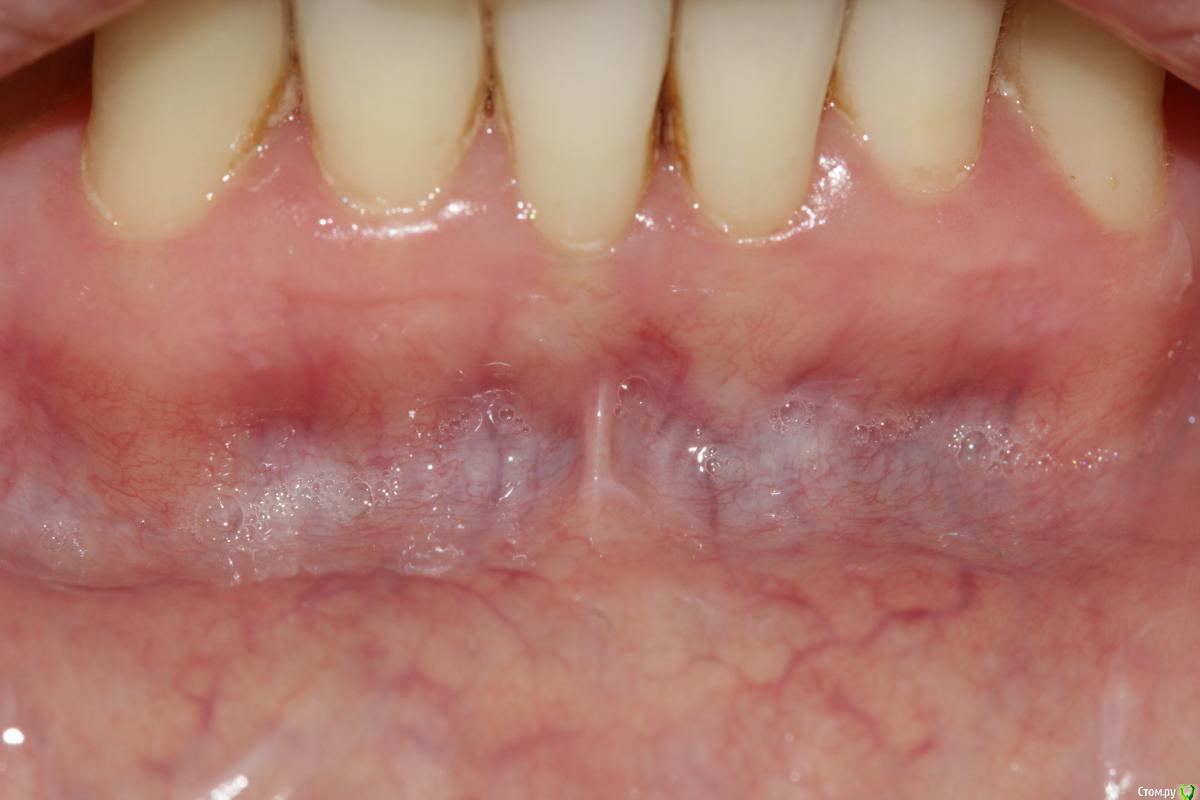

Dc.Petrov Опубликовано 12 февраля, 2015 Автор Поделиться Опубликовано 12 февраля, 2015 Никаких показаний к хирургии нет Не согласен, мб на фото не видно, но СДС у 31,41 не более 1-2 мм от края маргинальной десны.При инфильтрации анестетика это особенно очевидно. Условия для рецессий есть. Надо было просто биотип утолщить Согласен вот два грубых рубца получили...тем самым, действительно, поспособствовали возможности рецессии ? Не совсем понял Ваше утверждение. Буду наблюдать в отдаленные сроки. Если Вам интересно продолжу тему с фото через 3, 6, 12 месВсех благодарю за комментарии Ссылка на комментарий

Владмир Опубликовано 12 февраля, 2015 Поделиться Опубликовано 12 февраля, 2015 Не согласен, мб на фото не видно, но СДС у 31,41 не более 1-2 мм от края маргинальной десны.При инфильтрации анестетика это особенно очевидно. Условия для рецессий есть. Согласен ? Не совсем понял Ваше утверждение. Буду наблюдать в отдаленные сроки. Если Вам интересно продолжу тему с фото через 3, 6, 12 месВсех благодарю за комментарииКакие условия для рецессии? Тонкий биотип разве является причиной рецессий? Пациент прожил сколько лет и рецессий нет а тут вдруг должна роявиться 5 Ссылка на комментарий